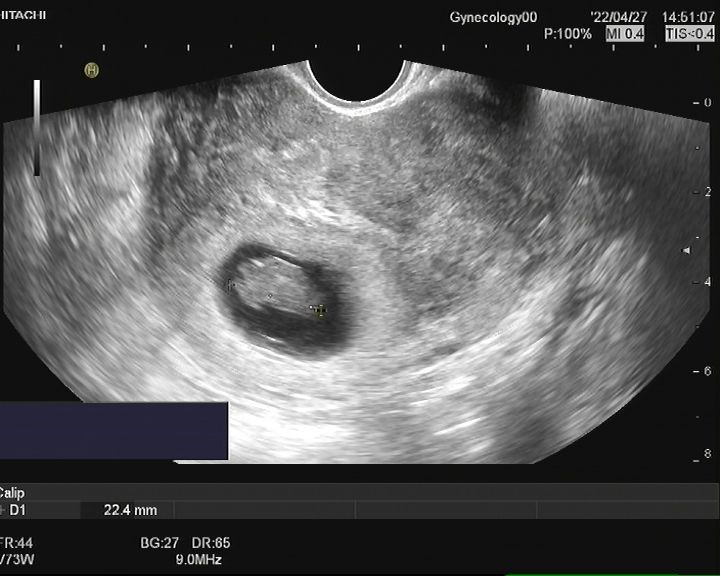

患者女,28岁,2021-06-07于青岛市妇女儿童医院就诊。 主诉:进行性痛经加重3年余。 现病史:患者月经初潮即有经期下腹痛,无需口服止痛药物。3年前痛经渐进性加重,目前经期腹痛VAS评分8分,伴恶心呕吐、肛周坠胀感。伴有非经期腹痛,VAS评分4分,持续4-5天,有深部性交痛。月经周期、经期及经量较前无明显改变。我院就诊超声提示:子宫后壁探及低回声结节,大小46mm*56mm*42mm,考虑子宫肌瘤。患者有明确生育要求,为求进一步治疗,门诊以“子宫腺肌病?子宫肌瘤?”收入院。患者自发病以来,神志清,精神可,饮食正常,经期夜间睡眠欠佳,体重较前无明显增减。 既往史:体健,否认慢性病及传染性疾病病史,否认外伤史,否认输血史,否认食物、药物过敏史。 月经及婚育史:既往月经规律,周期28-30天,经期5-6天,末次月经:2021-05-24。G1P0A1,2021年4月孕11周“稽留流产”行药物流产1次。 家族史:无特殊。 体格检查:T36.2℃,P77次/分,R18次/分,BP101/67mmHg,身高160cm,体重56kg。疼痛评分:0分。心、肺、腹部查体无异常。 专科查体: 妇科查体:外阴发育正常,阴道畅,宫颈光滑,子宫后位,增大如孕2月,固定、活动差,无压痛,双侧附件区未及异常。三合诊:左侧骶韧带触及触痛结节。 辅助检查: 2021-06-03 B超:子宫后位,宫体大小正常,形态规则,肌层内回声欠均匀,后壁肌层探及低回声结节,大小约46mm*56mm*42mm,边界清。宫腔内膜受压前移,厚10.1mm。宫颈形态正常。左侧卵巢探及液性暗区,大小约39mm*29mm,透声好,右侧卵巢大小正常。右侧附件区未见明显异常。 2021-06-07 肿瘤指标:糖类抗原CA19-9 52.21U/ml;糖类抗原CA125 112.9U/ml ↑; 2021-06-07 MRI提示:子宫后壁子宫腺肌病、盆腔子宫内膜异位症? 初步诊断: 2.盆腔子宫内膜异位症 3.不良孕产史 1.2021-06-08在镇静镇痛下行聚焦超声消融手术(FUAS)治疗。术后增强核磁检查提示子宫后壁腺肌病灶内无灌注区,子宫内膜及浆膜血流灌注正常。 2.2021-06-22术后第一次月经来潮,痛经较前减轻,VAS评分2-3分。术后辅助GnRh-a治疗3周期辅助治疗,同时口服钙片补钙治疗,用药期间闭经,无腹痛等不适。 3.GnRh-a治疗3周期后,2021-09-08复查B超:子宫后位,宫体大小正常,形态规则,肌层内回声欠均匀,后壁肌层探及高回声团,大小约38mm*37mm*26mm,边界清,内见少许血流信号。宫腔内膜受压前移,厚4.1mm。宫颈形态正常。双侧卵巢大小正常。双侧附件区未见明显异常。 4.2021-11-22月经复潮,经量正常,痛经VAS 2分,月经第5天开始口服地屈孕酮20mg QD,每月经周期20天,建议试孕半年。 5.2022-04-27随访复查,LMP:2022-02-24,停经9周,B超:子宫后位,体积增大,形态饱满,被膜光滑,后壁肌层回声不均匀,内见低回声区,较大范围约35mm*26mm,宫腔内见大小约32mm*31mm*24mm妊娠囊,张力可,内见胎芽,纵径22.4mm,心管搏动规律,妊娠囊下方探及不规则液性暗区,范围约21mm*8mm。双侧附件区未见明显异常。继续口服地屈孕酮10mg q8h保胎治疗。孕期进展顺利,2022-11-25外院足月剖宫产1女婴,体重3300g,Apgar评分10分-10分。 子宫内膜异位症和子宫腺肌病是妇科常见疾病。除了引起疼痛和月经改变,越来越多的证据表明,这两种疾病对女性的生殖功能有重要影响。临床可表现为不孕不育和流产等,尤其是早期流产[1]。 本例患者B超提示“子宫肌瘤”可能,但后续评估更符合子宫腺肌病。弥漫性子宫腺肌病的超声检查准确性较高,但子宫腺肌瘤超声表现与子宫肌瘤相似,临床诊断需要结合患者的症状、CA125水平综合判断。相比超声,磁共振检查对子宫腺肌病的分型更有优势,也更容易发现合并的盆腔子宫内膜异位症。后位子宫的后壁腺肌病灶往往合并子宫直肠陷凹的内异病灶,本例患者即属于该情况,治疗策略应兼顾两种疾病并同时考虑患者的生育需求。 针对子宫腺肌病,传统的病灶切除手术对子宫损伤较大,合并盆腔子宫内膜异位症时,手术操作也较困难,所以对于有生育需求的患者选择手术治疗需要相当慎重。聚焦超声消融术(HIFU)可选择性消融子宫腺肌病病灶、使病灶缩小,同时保护子宫完整性,从而达到减轻症状、缩小病灶、改善生育的目的[2]。但无法同时消融盆腔子宫内膜异位病灶,需要联合药物综合治疗。 子宫腺肌病和子宫内膜异位症的慢病管理理念已逐渐被认可,药物治疗是基石。而目前一线用药促性腺激素释放激素激动剂、地诺孕素等均会抑制排卵,有生育需求的患者备孕时需要停药。而停药后的试孕期病灶复发和进展风险较高,从而影响妊娠几率。地屈孕酮10-20mg/d可缓解内异症痛经,不抑制排卵,兼顾子宫腺肌病和盆腔子宫内膜异位症患者的治疗和备孕。此外,对于疑有黄体功能不足者黄体期使用地屈孕酮还可能提高自然受孕率,备孕期周期性用药副作用低,安全性高。 子宫腺肌病不仅可导致患者的生育力低下,诸如排卵障碍、不孕、流产、早产、死产、胎儿生长受限等,还可导致妊娠期母亲并发症如剖宫产率增加、子痫前期、前置胎盘及胎盘早剥等[3],一旦妊娠应更加积极的给予保胎治疗和严密随访,积极补充孕酮以抑制子宫平滑肌收缩,尽可能提高活产率。 子宫腺肌病和子宫内膜异位症具有类似的发病机制,也常常合并存在,严重影响女性的生殖健康。针对两种疾病的治疗应规范化、个体化、微创化。给予规范用药或手术治疗,减灭和消除病灶,减轻临床症状的同时,应充分考虑患者的主要诉求、年龄和生育需求,尽可能选取创伤小的治疗方式。重视患者全生命周期的管理,早诊早治、促进生育、长期管理预防复发,避免反复手术带来的创伤,定期随访,警惕恶变。 该患者28岁,痛经伴非经期腹痛,临床诊断符合子宫腺肌瘤合并子宫内膜异位症。既往不良孕产史,有明确生育需求,具有治疗指征。针对后壁子宫腺肌瘤传统手术方式对子宫损伤较大不利于患者后续妊娠,康医生选择了聚焦超声消融术治疗缩小子宫腺肌病病灶,减轻患者痛经并改善子宫形态,有利于提高妊娠几率。 子宫腺肌病和子宫内膜异位症在年轻患者中复发几率极高,可谓“不死的癌症”,当患者又有生育需求时,如何兼顾治疗和生育确实给我们提出了较高的要求。该患者在停用GnRh-a后月经来潮,备孕期间给予口服地屈孕酮稳定病灶、改善痛经,同时不会影响下丘脑-垂体-卵巢轴(HPO轴)而抑制排卵,还能提高自然受孕几率,可谓一举两得。 患者服用地屈孕酮3个月后便顺利妊娠,体现了治疗的有效性。更难能可贵的是,康医生重视子宫腺肌病患者的孕期管理,妊娠后继续给予口服地屈孕酮积极保胎,抑制子宫平滑肌收缩,也体现了将子宫腺肌病患者作为高危孕产妇管理的治疗理念。 参考文献: